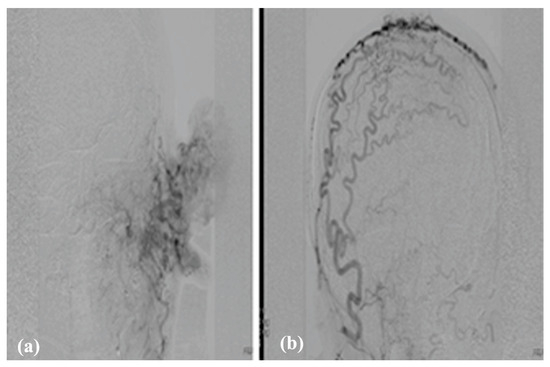

3.3.3. Therapy